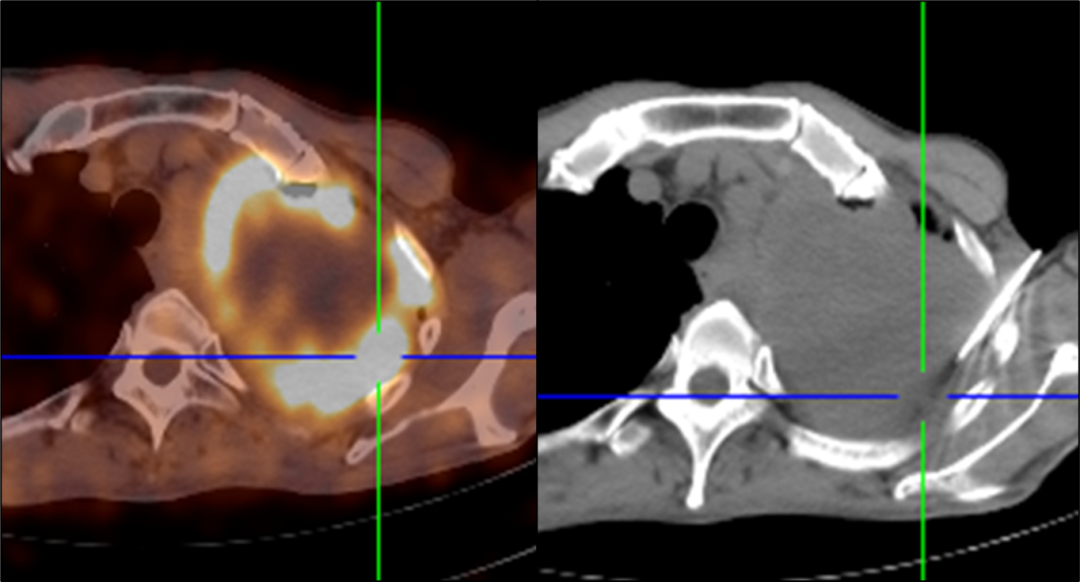

六、PET / CT引導下經皮穿刺活檢

CT引導下經皮穿刺活檢術是微創獲取腫瘤組織的重要手段,配合18F-FDG、18F-FAPI、18F-PSMA PET等功能影像精準識別腫瘤活性區域,能夠進一步提高手術的準確率及安全性。PET / CT引導下經皮穿刺活檢術適用于肺、肝、腎臟及前列腺等臟器腫瘤病灶的組織獲取,效果要顯著優于傳統CT引導的效果,是目前極為先進的活檢技術手段。2022年8月,哈爾濱醫科大學附屬第一醫院核醫學科在省內率先開展此項檢查,填補了省內PET引導下穿刺活檢術的空白,進一步實現了以患者為本的精準醫療(圖8)。

圖8 PET / CT引導下精準穿刺活檢腫瘤代謝活躍區